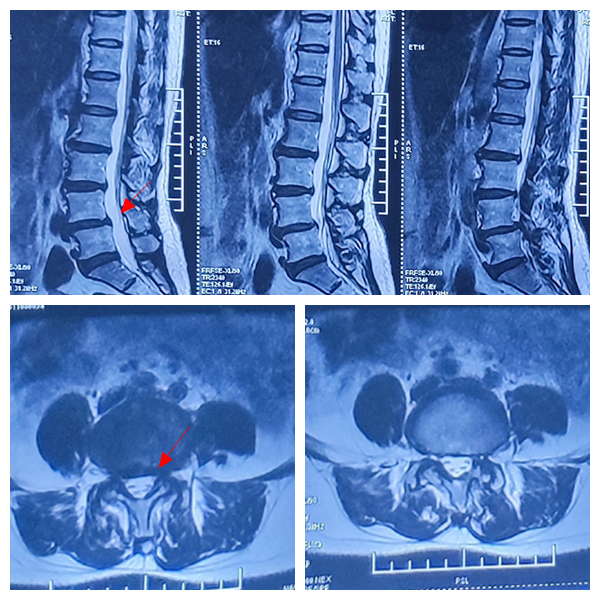

术前DR检查显示腰4椎体一度滑脱

术前腰椎核磁共振检查

显示腰4-5节段椎管狭窄